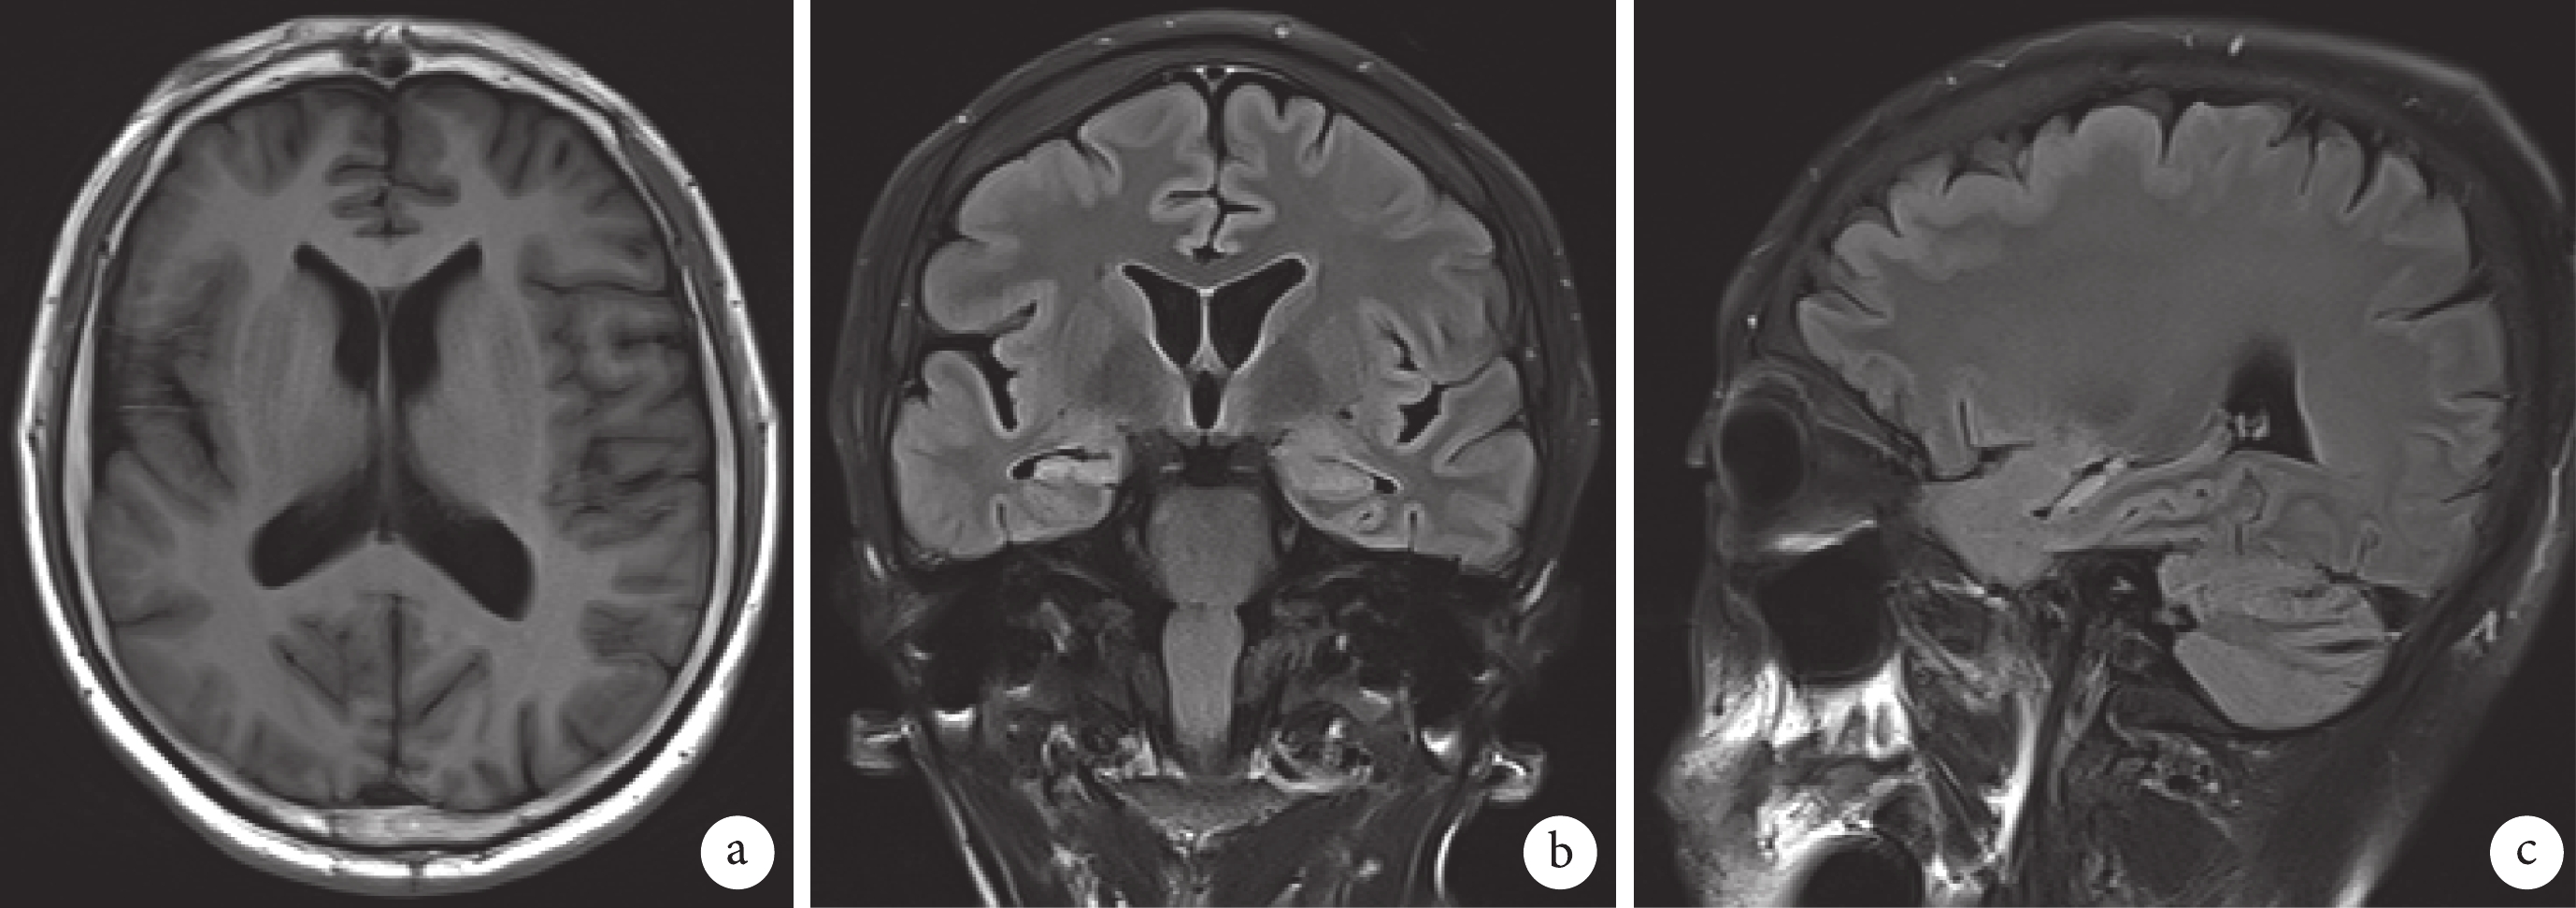

患者 男,32歲,抽搐發作病史13年余。a,b,c. T2-flair軸位、冠、矢狀位示右側巨腦回,雙側海馬體積縮小,結構模糊,信號增高,右側為顯著,右側杏仁核萎縮、信號增高

Figure1. Hippocampal sclerosis accompanied by right brain dysplasiaPatient, male, 32 years old, had a history of convulsions for more than 13 years. a, b, c. T2 flair axial position, coronal and sagittal positions show the right giant gyrus. The volume of bilateral hippocampus is reduced, the structure is blurred, the signal is increased, which is significant on the right, the amygdala atrophied and signal are increased on the right

135例海馬硬化患者中MRI掃描顯示單純性海馬硬化109例,伴有其他病灶的海馬硬化26例,其中伴有海綿狀血管瘤8例、外傷性或感染性軟化灶9例、局灶性皮層發育不良2例、腦裂畸形1例、巨腦回1例(圖1)、圍產期缺血缺氧所致白質減少并伴有軟化灶5例。海馬硬化MRI掃描檢查影像特點為:① 海馬體積略增大,結構模糊, T2-flair顯示海馬信號略增高,脈絡膜裂及顳角略變窄15例,占11.11%;② 海馬結構模糊,T2-flair呈斑點狀高信號,體積無變化17例,占12.59%;③ 海馬體積縮小,固縮成小團塊狀,T2-flair序列呈高信號,脈絡膜裂及顳角略擴大(圖2)103例,占76.30%。78例海馬硬化患者伴有乳頭體、穹隆、杏仁核及海馬旁回出現不同程度萎縮。